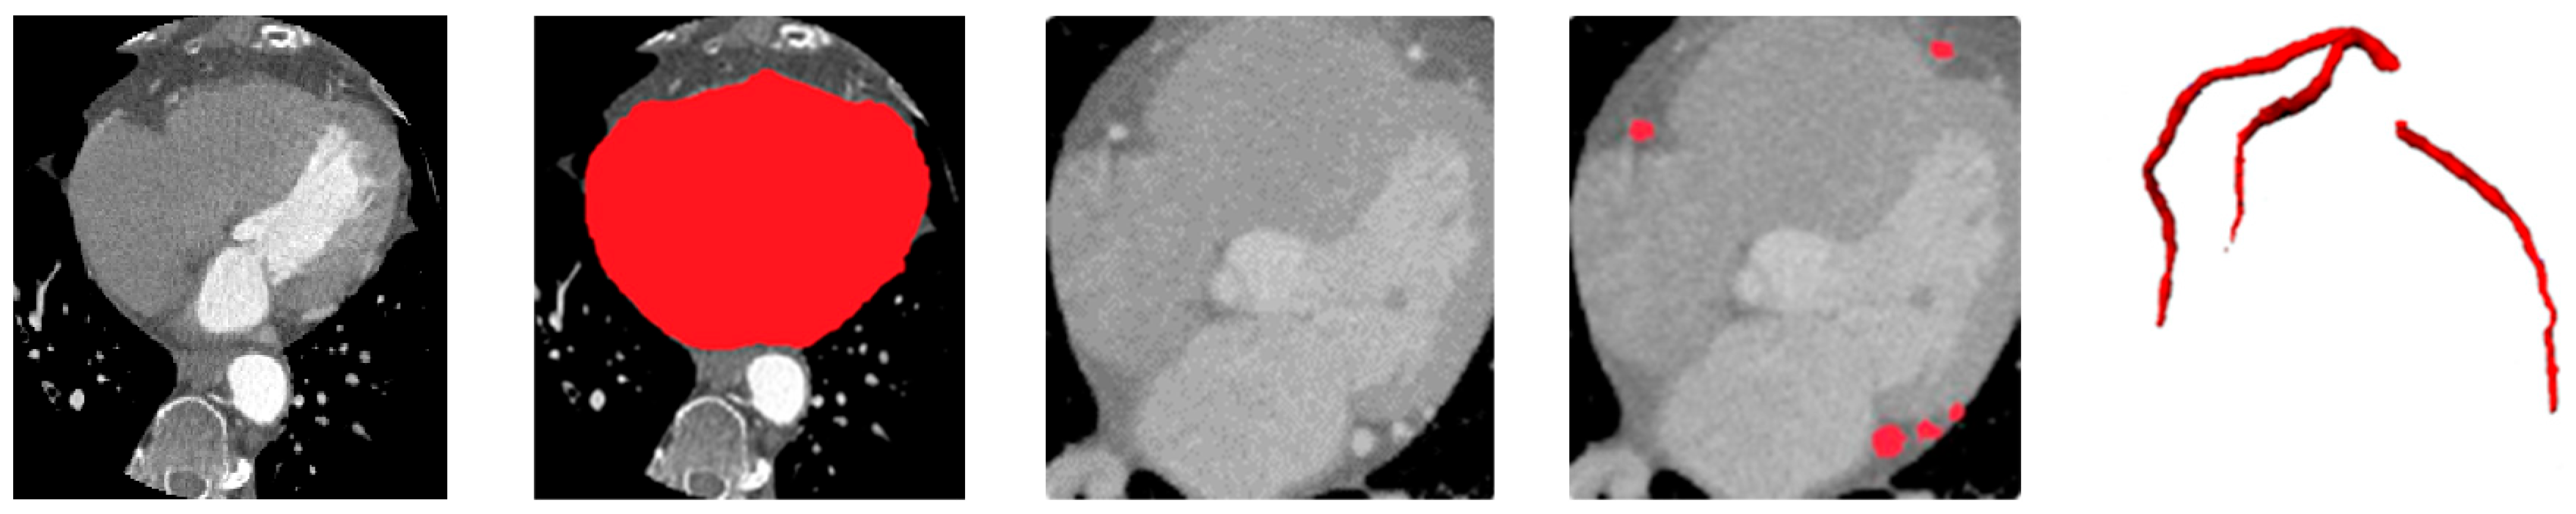

Figure 7. Comparison of fusion strategies for ensemble CAC segmentation. From left to right: rank-based selective ensemble output, soft-voting ensemble.

To evaluate the effectiveness of the proposed rank-based selective ensembling, we compared it against the conventional soft-voting approach, where probability maps from all ensemble members are averaged voxel-wise without spatial weighting. While simple, soft-voting treats all model predictions equally, regardless of their local anatomical plausibility or consistency, often leading to over-segmentation and blurred lesion boundaries.

As shown in Table 3, the proposed selective fusion achieves higher Dice and sensitivity while maintaining high specificity. This improvement stems from the ability of the rank-based strategy to evaluate predictions based on morphological consistency, spatial continuity, and vessel conformity. By ranking each candidate prediction relative to the vessel priors obtained in the preceding stage, the method selectively emphasizes anatomically reliable regions while suppressing fragmented or false detections outside the coronary tree.

The selective ensemble improves Dice by approximately +0.55% and sensitivity by +0.6% compared to soft-voting, demonstrating that spatially guided, vessel-aware weighting is more effective than uniform averaging. This enhancement is most evident in small or low-density calcifications, where anatomical context plays a critical role in distinguishing true lesions from background noise.

Visually, the selective ensemble produces sharper and smoother lesion boundaries and exhibits fewer false positives, especially around dense extracardiac regions such as the aorta and cardiac valves.

Figure 7 presents representative qualitative comparisons, illustrating that the selective fusion generates cleaner, anatomically coherent segmentation masks, effectively preserving true calcifications while suppressing spurious predictions. The proposed selective fusion produces more anatomically consistent calcification masks with reduced false positives and improved boundary continuity.